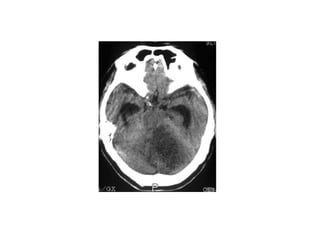

Brain stem strokes

• Although rare, brain stem strokes can be devastating.

Signs and symptoms differ with the specific stroke

location, but may include hemiparesis or

quadriplegia, sensory loss affecting either the

hemibody (half of the body) or all four limbs, double

vision, dysconjugate gaze, slurred speech, impaired

swallowing, decreased level of consciousness, and

abnormal respirations. Patients with brain stem strokes

are likely to be critically ill and may require emergency

intubation and mechanical ventilation.

Brain stem strokes •Although rare, brain stem strokes can be devastating. Signs and symptoms differ with the specific stroke location, but may include hemiparesis or quadriplegia, sensory loss affecting either the hemibody (half of the body) or all four limbs, double vision, dysconjugate gaze, slurred speech, impaired swallowing, decreased level of consciousness, and abnormal respirations. Patients with brain stem strokes are likely to be critically ill and may require emergency intubation and mechanical ventilation.